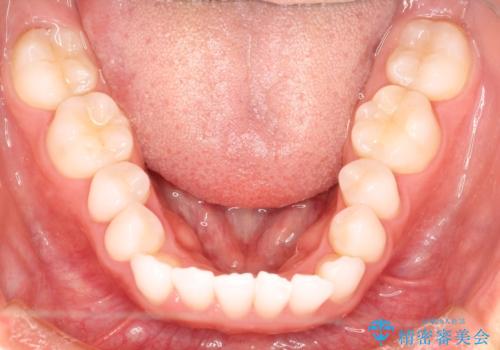

気になる前歯の歯並びをインビザラインで矯正

- 前歯の傾きと、ガタガタが気になるとのことで来院されました。

前歯の傾きや高さをシミュレーションで患者様と確認しながら、歯並びを仕上げていきました。